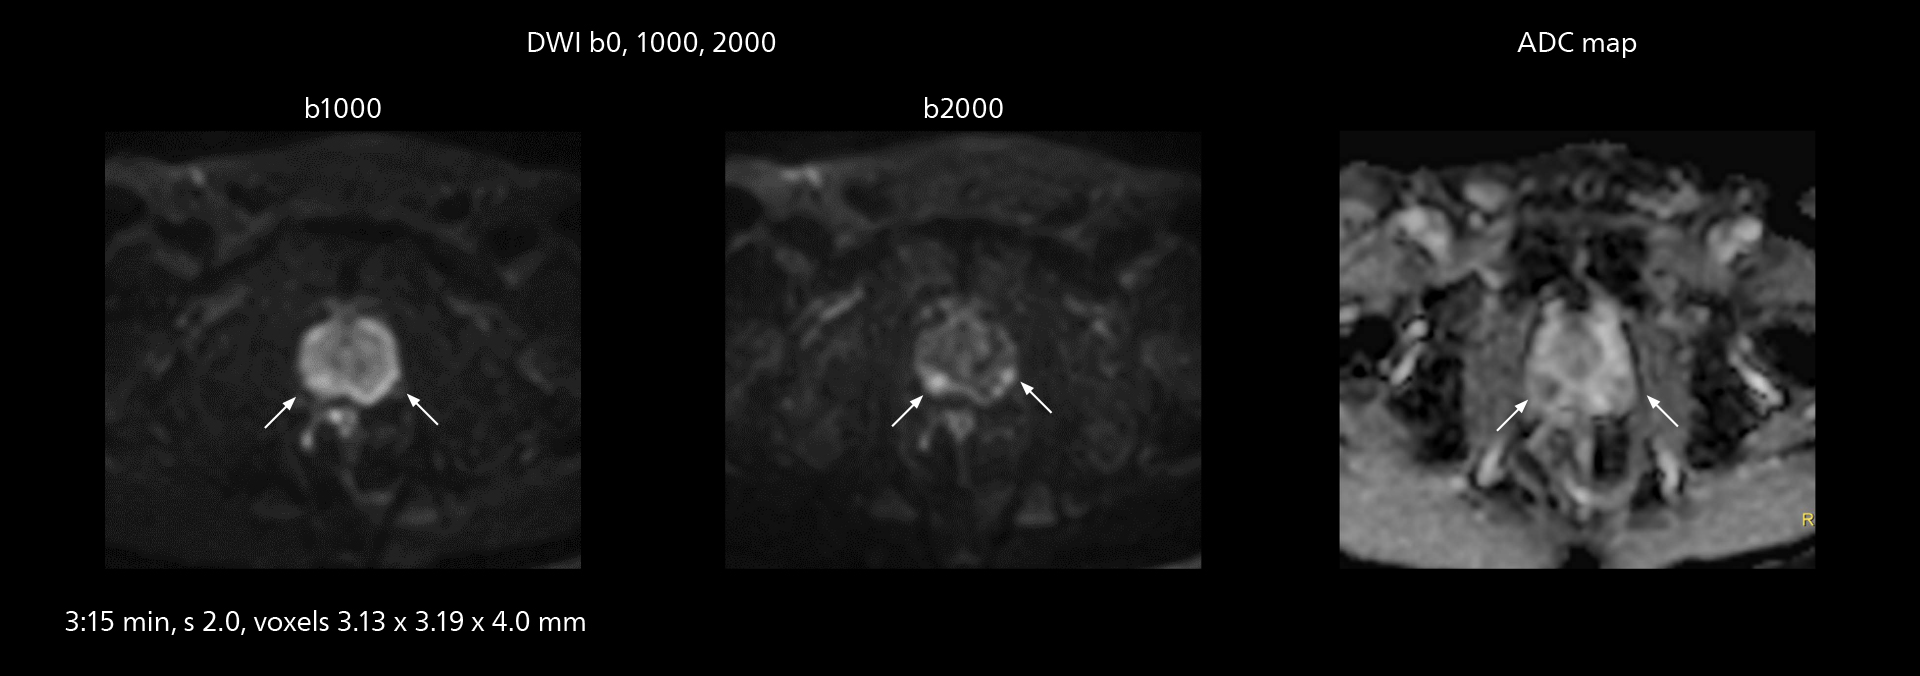

The high performance of the Vega HP gradients is particularly impressive in DWI. “The Vega HP gradients enable us to scan faster and use b-values as high as 2000, for example in prostate DWI and in DWIBS, which provides image quality that is remarkably improved over the previous system and we are able to more easily see lesions.”

Examples of prostate imaging showing faster scan times and improved resolution illustrate the power of SmartPath to Elition X in this case of prostate cancer with PI-RADS score 4.